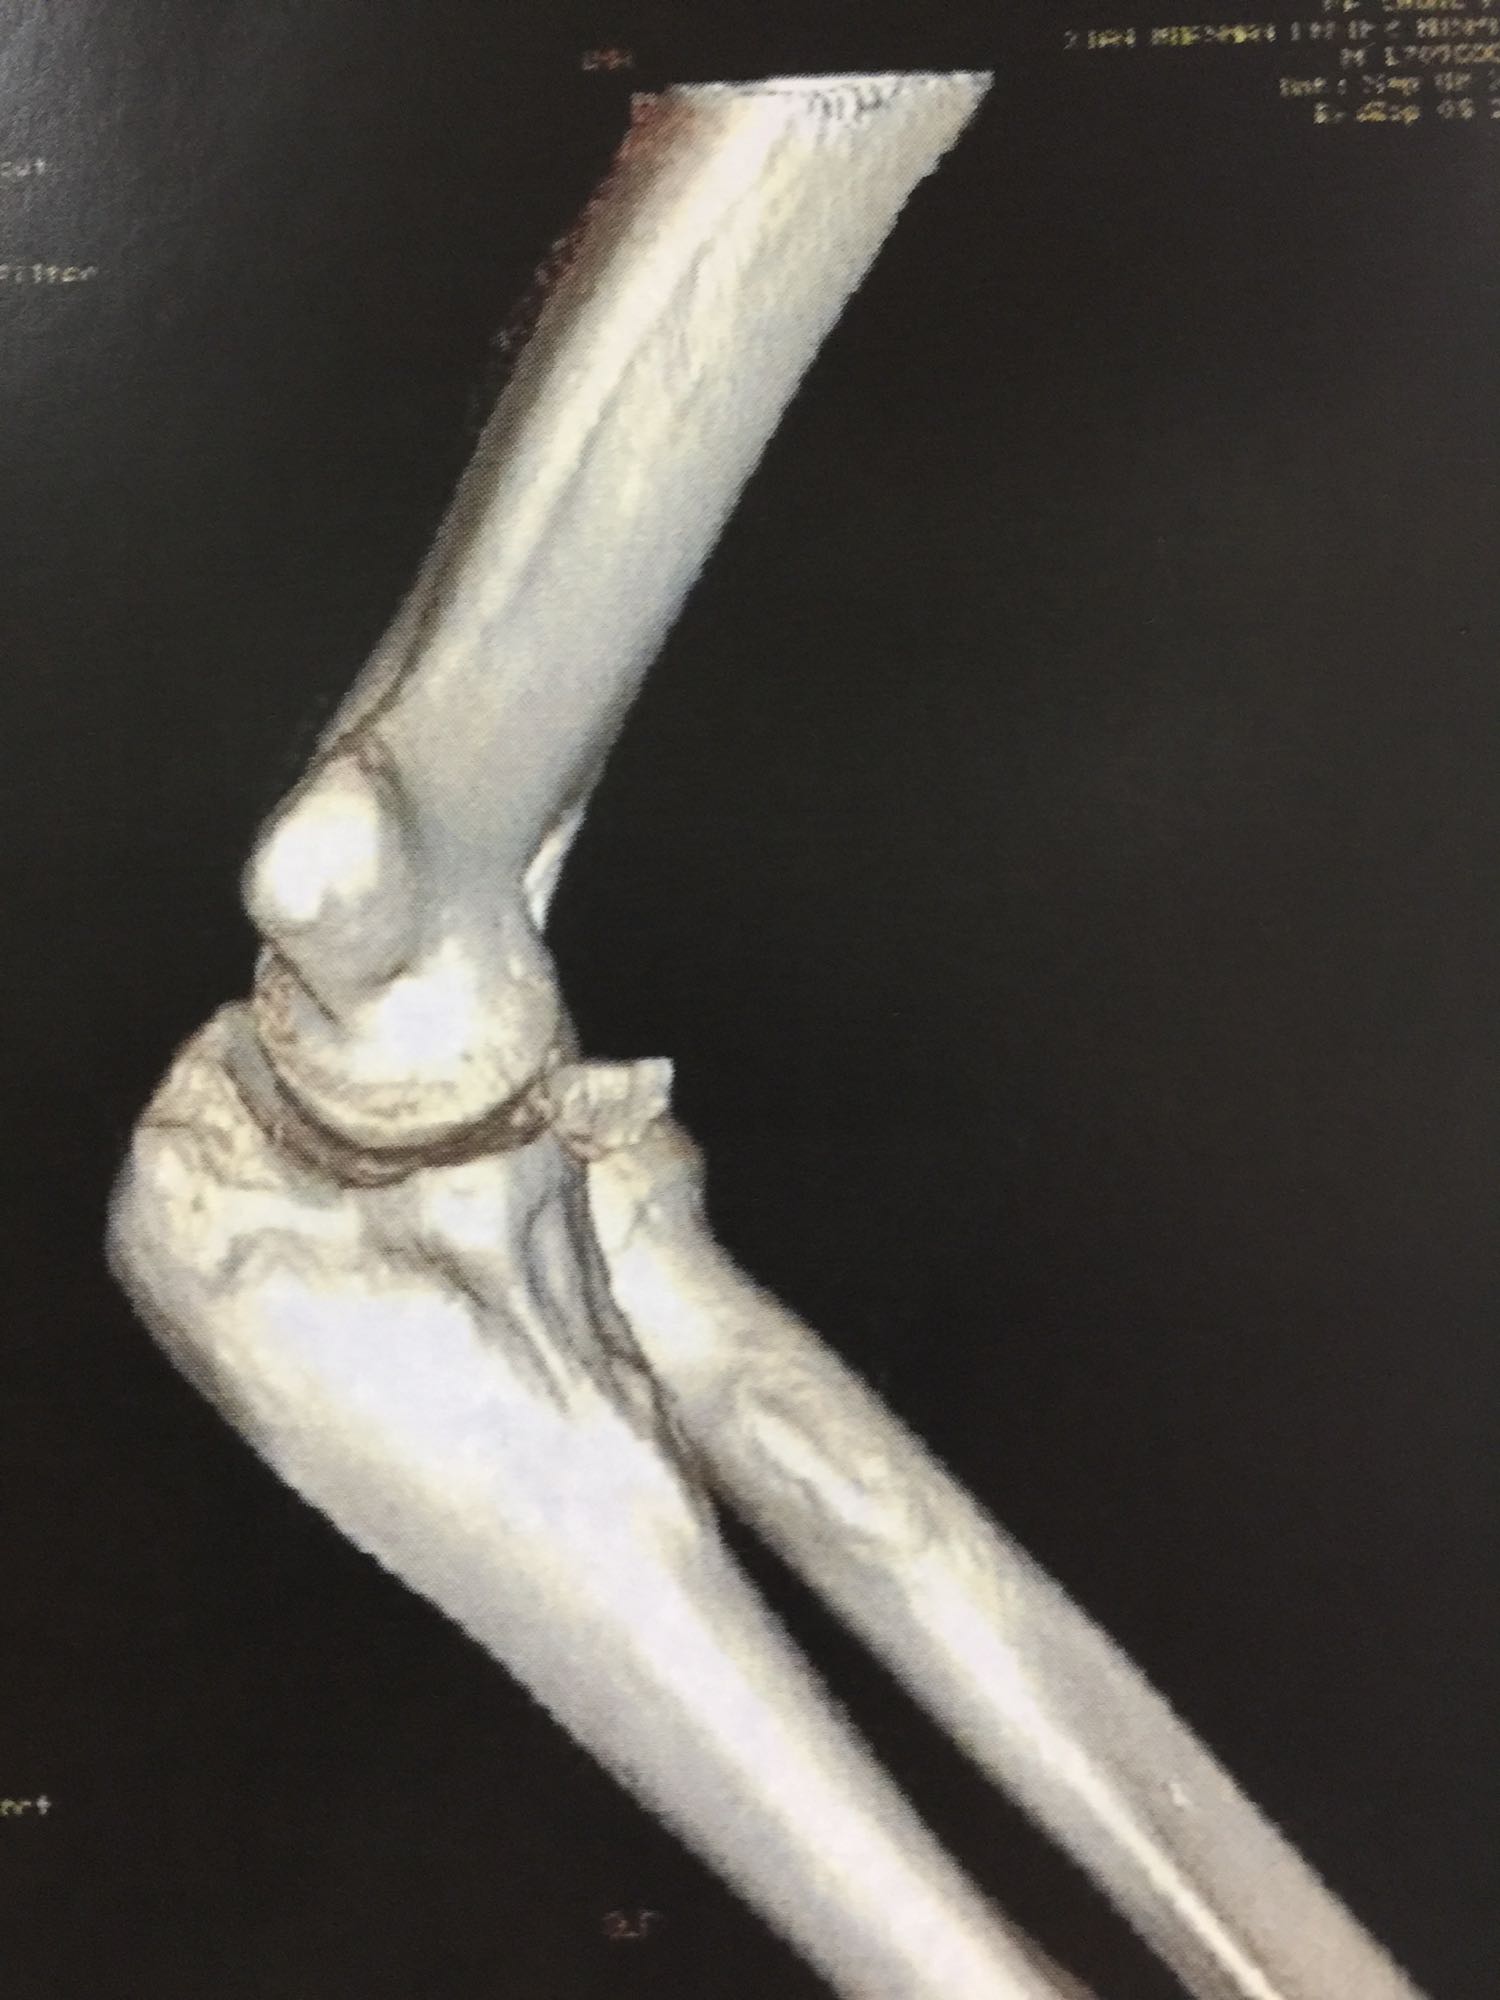

尺骨冠状突骨折合并肱骨外髁撕脱骨折

左肘关节高度肿胀,压痛强阳性,肘关节明显活动受限,末梢血运良好,各指关节运动正常。 X线片及CT如图:

1、左尺骨冠状突骨折;2、左肱骨外髁撕脱骨折 治疗:入院后伤肢石膏外固定,给予局部冷敷消肿治疗,于伤后一周行骨折手术治疗,先行前内侧切口复位固定冠状突骨折,活动肘关节发现关节明显不稳定,随取外侧切口,复位固定肱骨外髁,修补外侧副韧带,肘关节明显稳定。术中术后片子如下